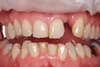

Remplacement par un implant

Cet implant supporte un pilier personnalisé en Zircon qui permet de soutenir la couronne

Résultat après 6 mois